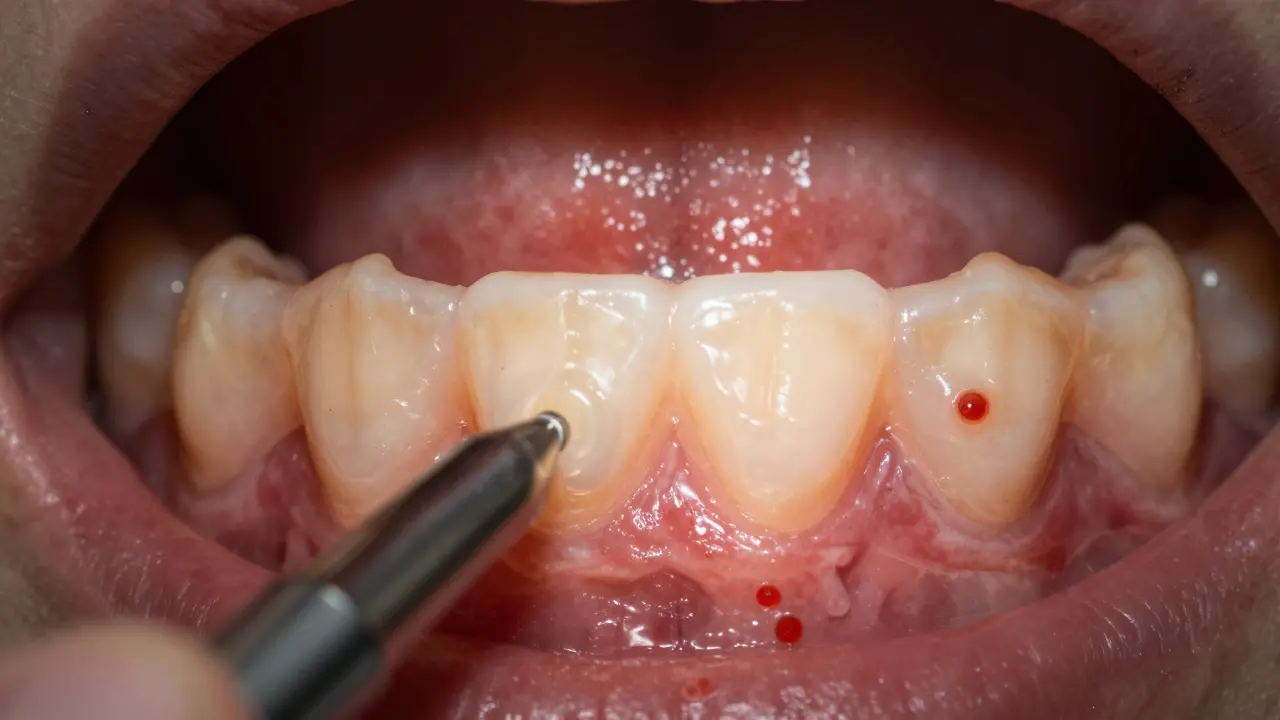

Bílé a červené skvrny na dásních při zubní prohlídce

• Červené nebo bílé skvrny - Leukoplakie (bílé skvrny) a eritroplakie (červené skvrny) na dásních mohou být předzvěstí rakoviny. Tyto skvrny nejsou bolestivé, ale mohou být hrubé nebo vytučnělé.

• Změny barvy dásní - Místa, která jsou mimořádně bledá, modravá nebo hnědá, by měla vyvolat podezření. Normální dásně mají rovnoměrnou růžovou barvu.

• Krvácení bez viditelné příčiny - Pokud dásně krvácejí při čištění zubů nebo v klidu, může to být příznak. Běžný zánět dásní způsobuje krvácení jen při špatné hygiene, zatímco rakovina může způsobit krvácení i bez vnějšího podnětu.